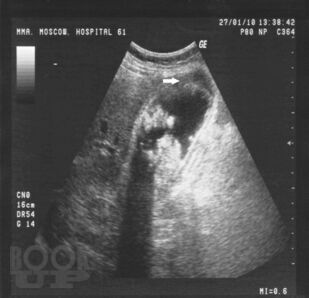

Учебно-методическое пособие посвящено актуальным проблемам этиологии, патогенеза, диагностики, современным методам консервативного и оперативного лечения острого холецистита. Представлены новые классификации, схемы консервативного лечения, современные виды оперативного лечения, учитывая утвержденные клинические рекомендации Российского общества хирургов (2015 г.). Издание иллюстрировано рисунками, таблицами, имеются тестовые задания и задачи. Пособие предназначено слушателей дополнительного профессионального образования и для ординаторов, обучающихся по специальности 31.08.67 Хирургия.